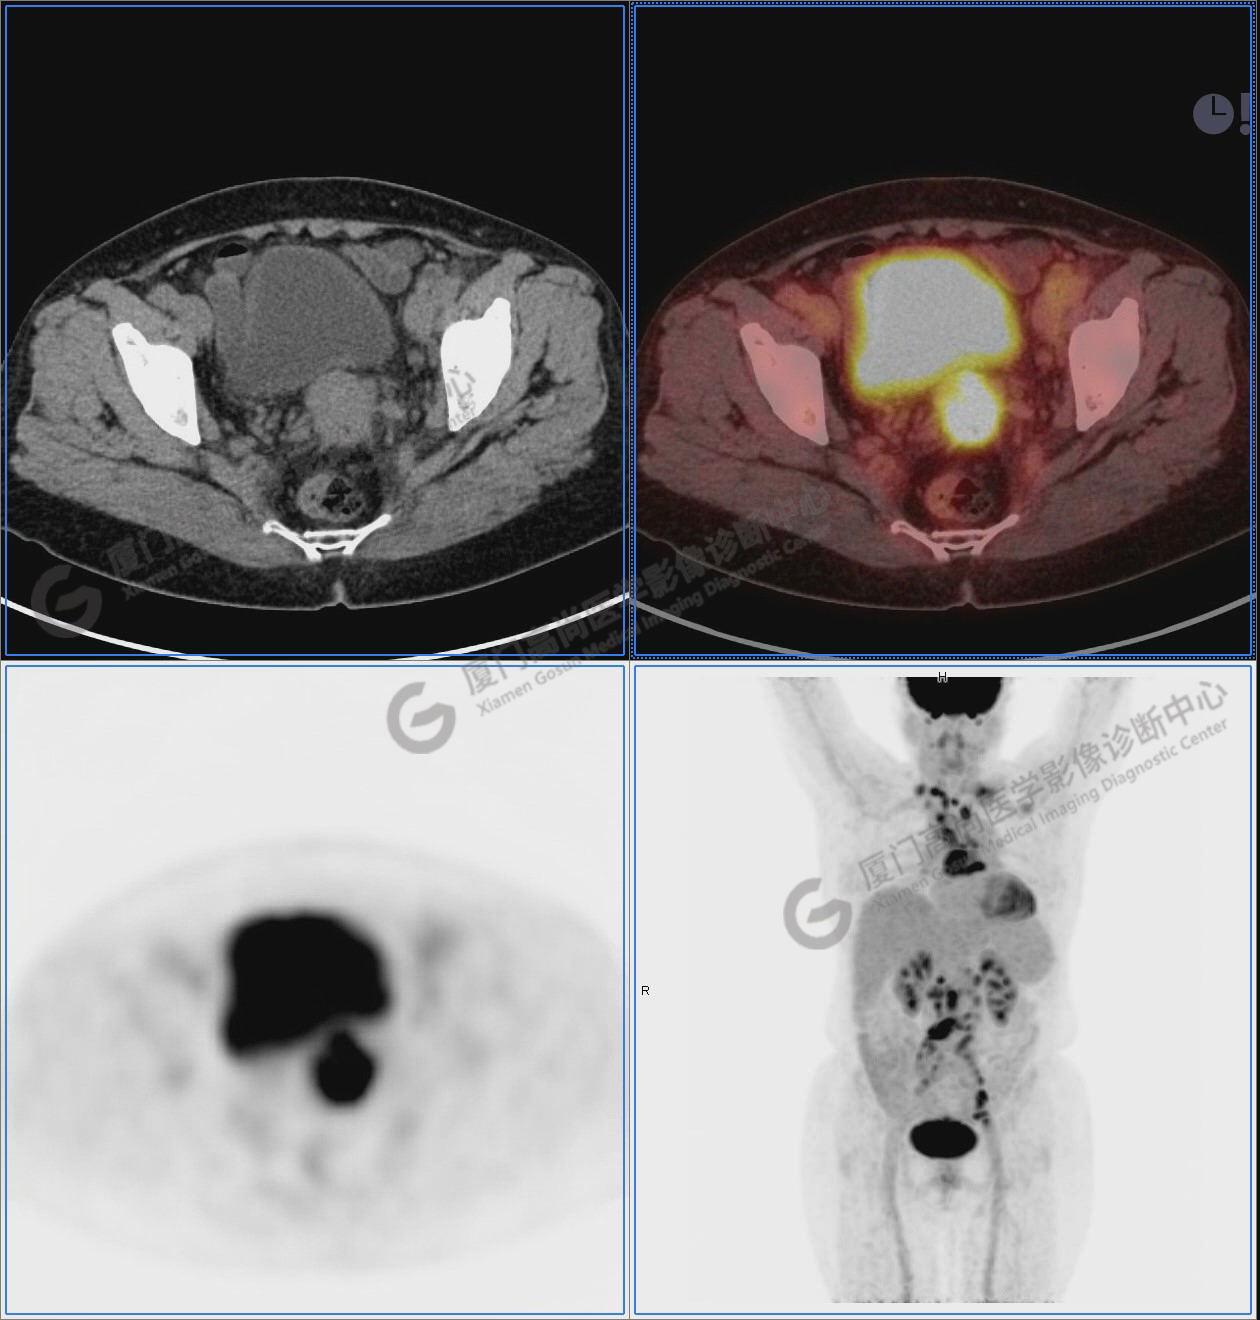

圖10-11:子宮頸軟組織腫塊,代謝異常增高,考慮為宮頸癌。

圖10

圖11